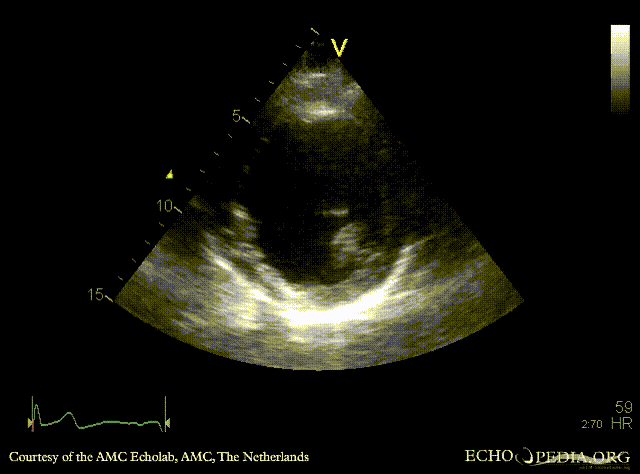

Apical aneurysm of LV

PLAX: dilated left ventricle, apical aneurysm PSAX: dilated left ventricle, reduced function